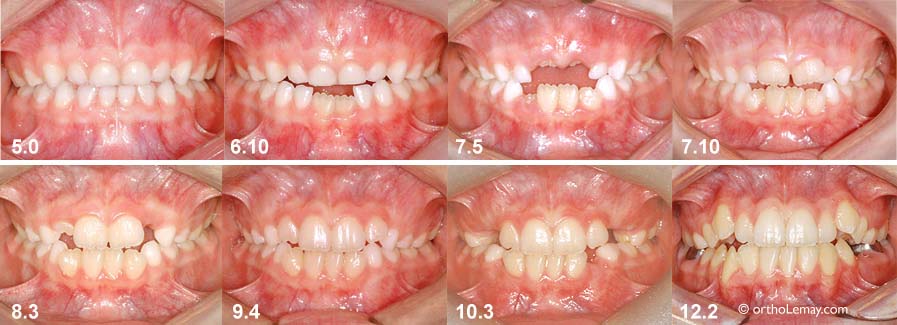

Développement de la dentition et de l’occlusion avec un stage de béance antérieure entre l’âge de 5 et 12 ans. À 6 ans 10 mois, les les centrales inférieures permanentes font leur éruption. À 7.5 ans, il y a une béance antérieure importante. Par la suite, à mesure que les incisives permanentes font leur éruption, la béance diminue pour finalement disparaître.

Cependant, une béance doit être considérée comme anormale lorsqu’elle persiste au-delà d’un stage de développement dentaire où les dents doivent normalement avoir fait éruption.